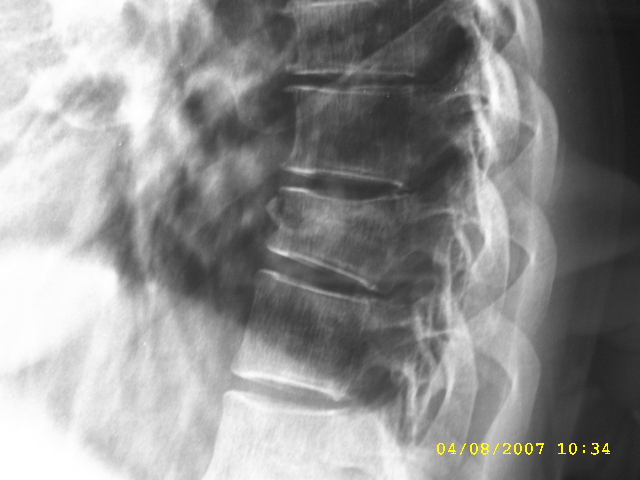

标题: CL0477:【】典型椎体压缩骨折

典型椎体压缩骨折

椎体压缩骨折,有碎骨片